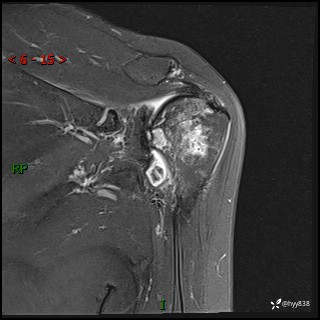

现病史:患者1月前无明显诱因出现左肩关节疼痛,于2024.07.31就诊于我院骨科门诊完善左肩关节MR:左肱骨头信号异常,肿瘤?建议进一步检查。左肩关节积液。左腋窝淋巴结增大。今为求明确诊断就诊我科,门诊以“骨质破坏”收入我科。 起病以来,精神食欲睡眠尚可,大小便正常,体力体重无明显变化。

肱骨MRI平扫(axi T1WI+cor T2WI-fs)+CE-fs(COR+SAG)